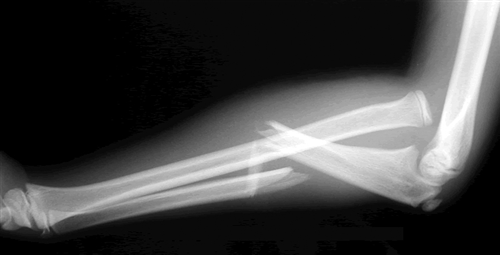

Monteggia injury

(fracture of the ulnar shaft and dislocation of the radial head at the elbow)

How are Monteggia fractures treated?

ORIF

(in adults and children)

A _________ fracture involves fracture of the ulnar shaft and dislocation of the proximal radial head at the elbow, whilst a __________ fracture involves a fracture of the radial shaft alongside dislocation of the ulna at the distal radio-ulnar joint

A Monteggia fracture involves fracture of the ulnar shaft and dislocation of the proximal radial head at the elbow, whilst a Galeazzi fracture involves a fracture of the radial shaft alongside dislocation of the ulna at the distal radio-ulnar join